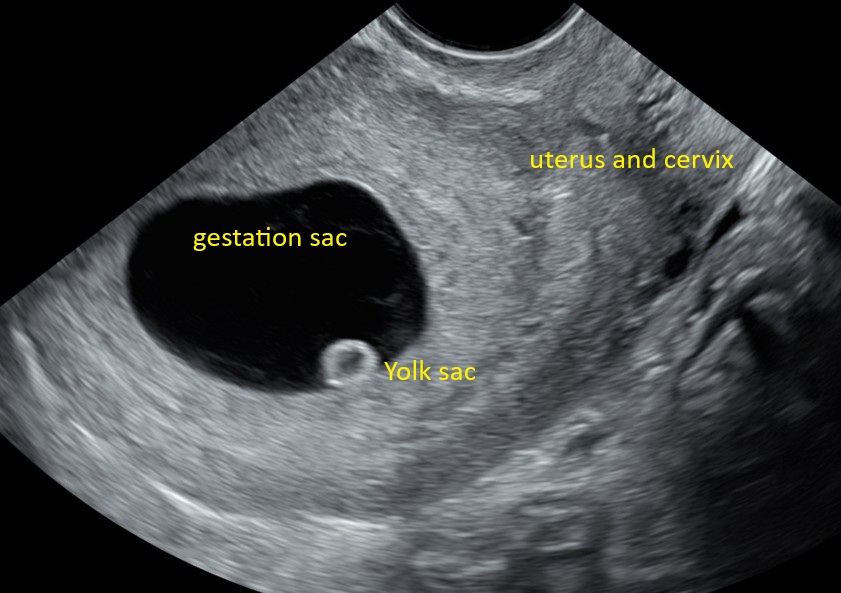

ANATOMY: We can see the yolk sac as early as 5 weeks, this is even before the baby is seen. This can also confirm the correct position of the baby but we will not see the baby at 5 weeks, thats why we recommended to come after 6 wks. Although, we will never say no if you want to check position. We also check the ovaries and the surrounding area to make sure there is no pathology.